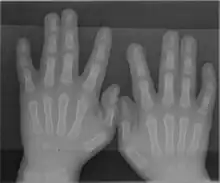

The somatosensory cortex representation of the hand is a dynamic reflection of the fingers on the external hand: in syndactyly people have a clubhand of webbed, shortened fingers. However, not only are the fingers of their hands fused, but the cortical maps of their individual fingers also form a club hand. The fingers can be surgically divided to make a more useful hand. Surgeons did this at the Institute of Reconstructive Plastic Surgery in New York to a 32-year-old man with the initials O. G.. They touched O. G.'s fingers before and after surgery while using MRI brain scans. Before the surgery, the fingers mapped onto his brain were fused close together; afterward, the maps of his individual fingers did indeed separate and take the layout corresponding to a normal hand.[27]

A rare anatomical variation affects 1 in 500 humans, in which the individual has more than the usual number of digits; this is known as polydactyly. A human may also be born without one or more fingers or underdevelopment of some fingers such as symbrachydactyly. Extra fingers can be functional. One individual with seven fingers not only used them but claimed that they "gave him some advantages in playing the piano".[28]